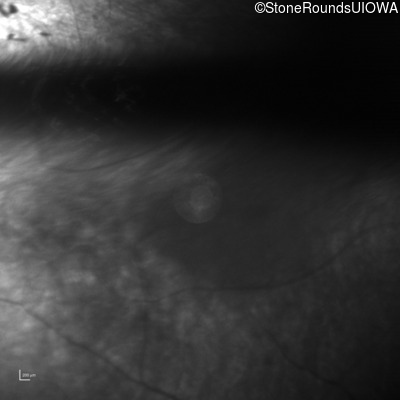

Infrared Fundus Photograph - Right - No Light Perception

Exemplar